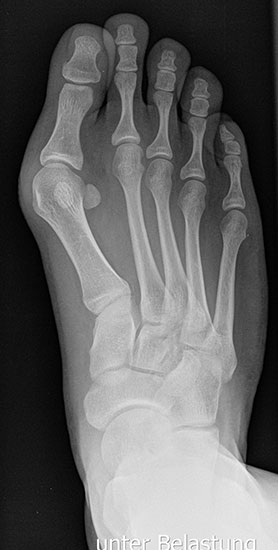

Bei einem juvenilen Hallux valgus handelt es sich um eine schon im Kindes – oder Adoleszentenalter 1 bestehende Valgusdeviation der großen Zehe bei Spreizfuß mit vergrößertem Intermetatarsalwinkel I / II aufgrund einer Adductionsstelllung des Metatarsale I – Metatarsaus primus varus.

Im Gegensatz zum Hallux valgus des Erwachsenen ist die Valgusabweichung der großen Zehe meist geringer ausgeprägt als bei Erwachsenen, der Intermetatarsalwinkel oft stark vergrößert. Die Angaben ab wann der Intermetatarsalwinkel als vergrößert gilt schwanken zwischen > 9° 2 und >14°3. Das Ausmaß der Beschwerden korrelieren nicht mit dem Auftreten und dem Schweregrad der Deformität (Zollinger 1990, Zollinger 1993). Begünstigend wirkt eine Schrägstellung des ersten Tarsometatasalgelenkes (Hefti 1998) und eine Hypermobilität dieses Gelenkes 2 in Kombination mit einer Bindegewebsschwäche. Häufig liegt eine positive Familienanamnese vor. In einer Untersuchung von Coughlin fand sich eine Vererbung über die mütterliche Linie in 72%, ein milder bis stark ausgeprägter Knick-Senkfuß in 17% (das entspricht der Quote von Knick-Senkfüßen in der Normalbevöl­kerung) aber in 22% ein Pes adductus, das ist wesentlich mehr als in der Normalbevölkerung zu erwarten wäre 4. Auch für Hefti (1998) gilt der Pes adductus als Komponente des Sichelfußes als begünstigend. Zur Inzidenz des Hallux valgus juvenilis finden sich je nach Autor verschiedene Angaben. Nach Auswertung von Schuluntersuchungen liegt die Häufigkeit zwischen 1,6 % bis 17% 56. Häufig tritt die Fehlstellung doppelseitig auf. Der Anteil der betroffenen Mädchen liegt 4-5x höher als bei Jungen (Lamprecht 2015).

Röntgen

Standard ist die belastete Röntgenaufnahme des Fußes dorso-plantar und seitlich. Günstig ist eine Röhrenkippung von 10°-20°, um die Gelenke der Lisfranc-Linie einsehen zu können.

• Hallux valgus Winkel

• Hallux valgus interphalangeus Winkel

• Intermetatarsalwinkel I zu II

• Distaler Metatarsale Gelenkwinkel (PASA)

• Pes metatarsus adductus

• Wachstumsfugen